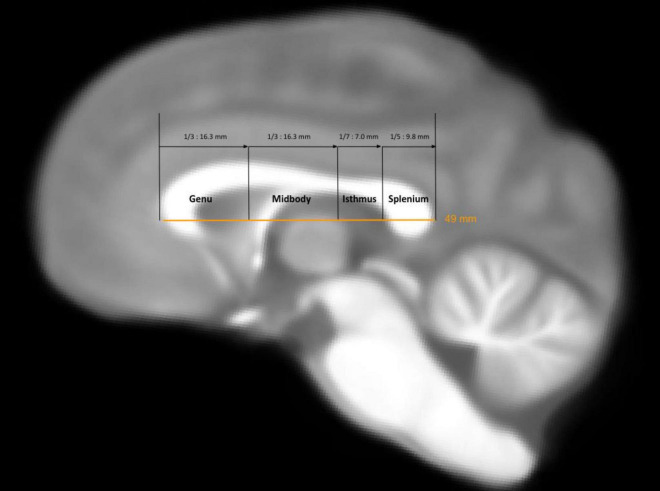

Studies on the human brain have emphasized the loss of gray matter volume and decreased thickness during normal aging, along with variations in the density of small axon fibers across different regions of the corpus callosum (CC). Here, we investigated age-related changes in white matter connectivity in the CC and their association with handedness and cognitive decline in chimpanzees. To this end, microstructural measures of CC morphology were obtained from a sample of 49 chimpanzees. Initial assessments included quantifying streamline density, fractional anisotropy (FA), axial diffusivity (AD), and radial diffusivity (RD) values, which were then correlated with age and cognitive measures using the Primate Cognition Test Battery. We found an inverse association between streamline density and age in chimpanzees, particularly in the anterior and central CC regions. We also found an inverse association between FA and age in the splenium. Lastly, after controlling for age and sex, chimpanzees with higher cognition values also had higher FA values in anterior regions of the CC. Collectively, our results show that chimpanzees diverged from the typical human pattern, suggesting stronger interhemispheric connectivity integrity in frontal cortical brain regions compared to humans.